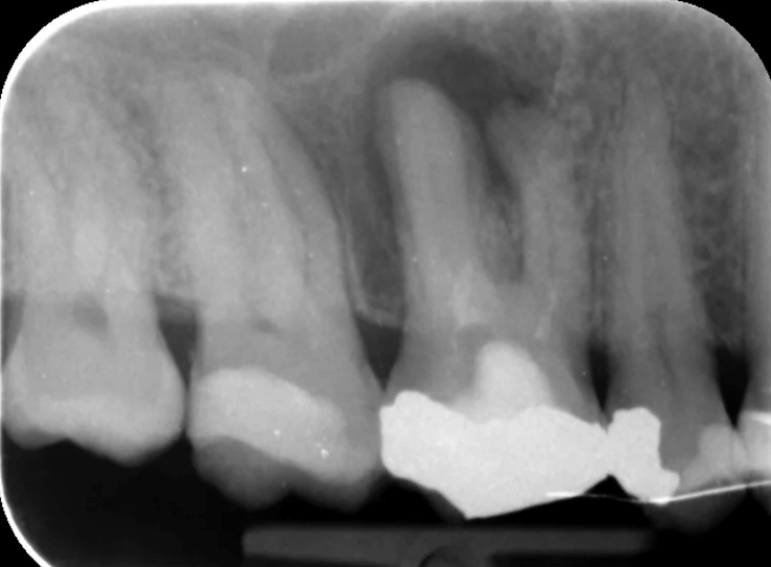

Root fillings, whitening and repair of two fractured incisors.